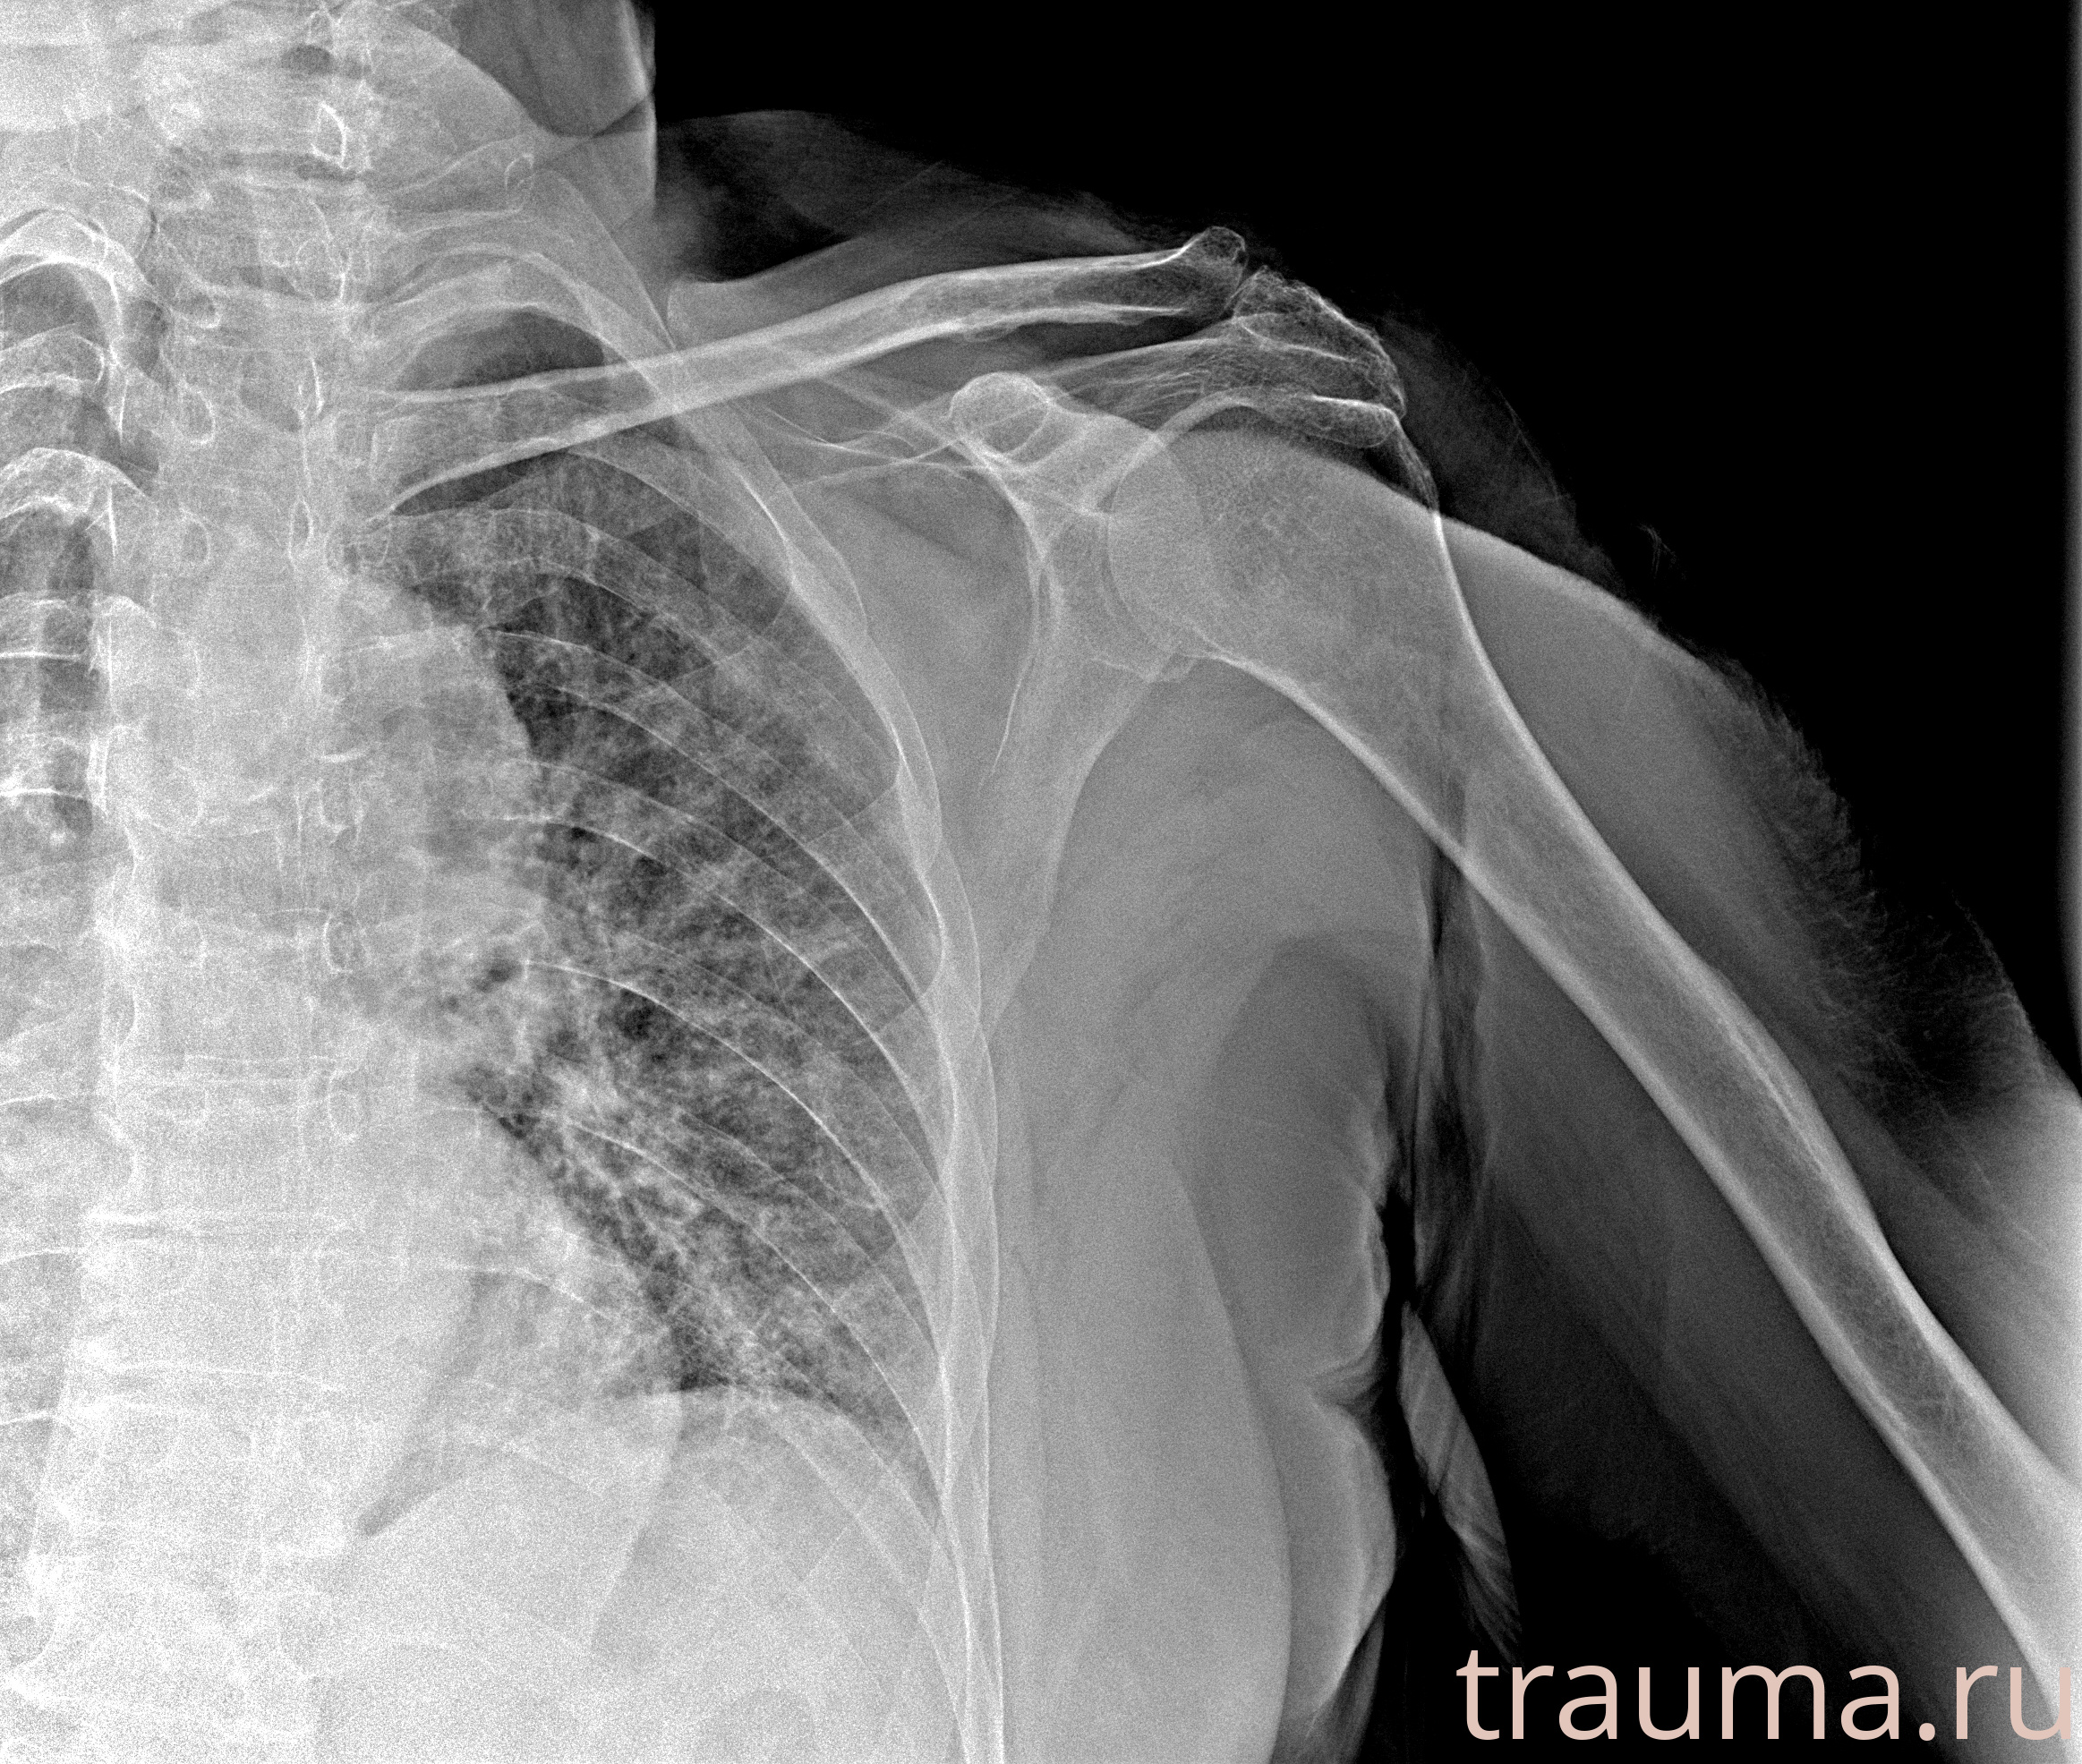

Рентген на дому: по вашему адресу приезжает врач-рентгенолог, травматолог-ортопед с мобильным рентгеновским аппаратом, проводит диагностику травмы или заболевания, делает необходимые рентгенограммы, дает рекомендации по дальнейшему лечению. Получить качественные снимки в домашних условиях возможно благодаря уникальной методике, разработанной МосРентген Центром для института  Склифосовского